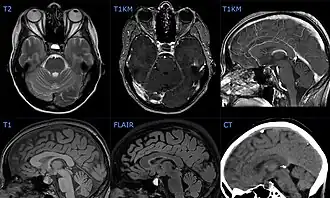

Description de l'image Hypophyseninfarkt mit Einblutung 44W - MR CT - 001 - Annotation.jpg.

Le diagnostic est suspecté sur la base des symptômes et confirmé par l'IRM [1]. Une ponction lombaire peut détecter du sang dans le liquide céphalo-rachidien [6].